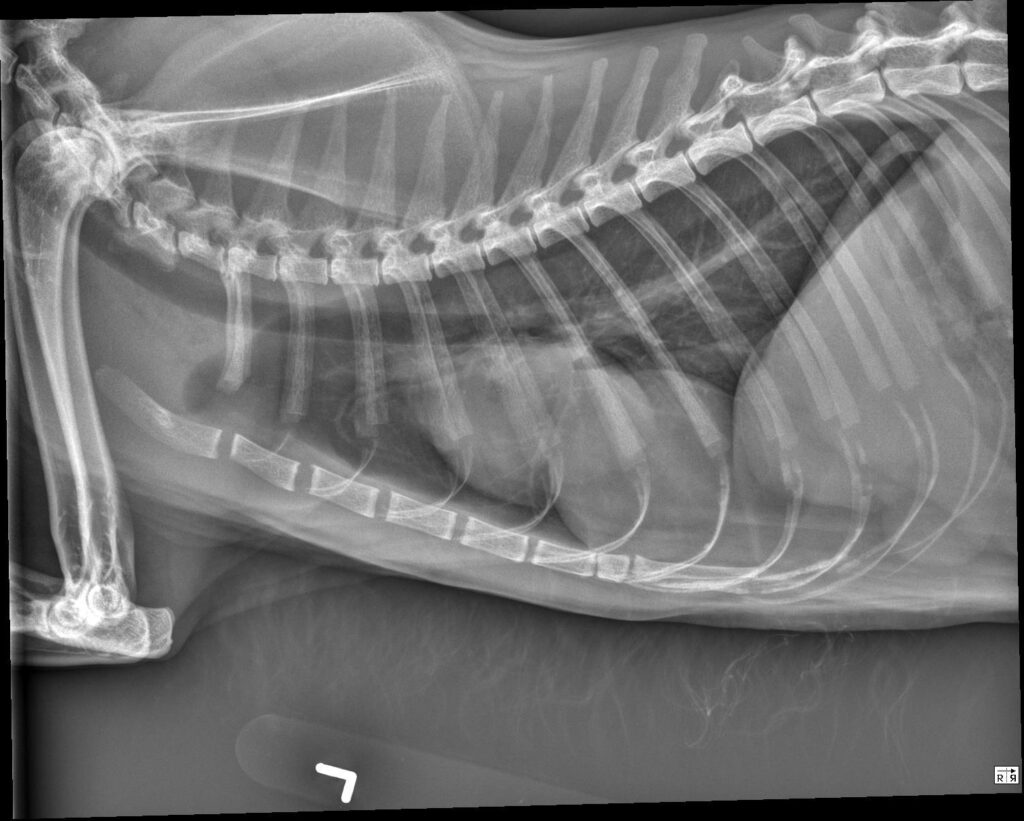

Radiology Quiz February 2026

History 2 year old labradoodle. Female Spayed. 2 weeks ago was diagnosed with aspiration pneumonia. Still lethargic.